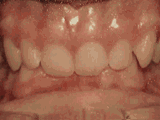

前牙移位,因为有牙齿缺失,导致相邻牙齿开始没有秩序的前突,经过矫正后是变成这样的~

前牙移位,因为有牙齿缺失,导致相邻牙齿开始没有秩序的左右移动,经过矫正后是变成这样的~

前牙移位,因为有牙齿缺失,导致相邻牙齿开始没有秩序的乱移动,经过矫正后是变成这样的~